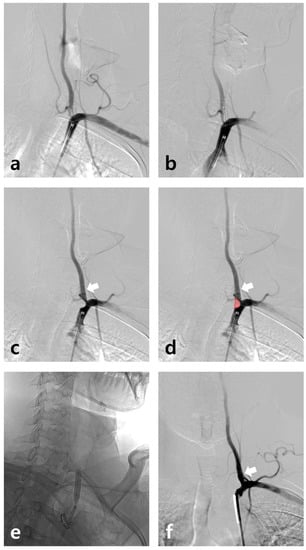

A 45-year-old male had suffered intermittent compressive left occipital headache radiating from the left shoulder for 5 years (10–15 days per month). His headache had worsened for a month (7/10 on the Visual Analog Scale). Brain computed tomography angiography showed severe stenosis at the orifice of the left vertebral artery (VA). A stent was inserted and the location of the balloon-mounted stent (Biotronik, Pro-kinteic Energy 5.0 × 13 mm) was confirmed under fluoroscopic guidance (Figure 1a,b). Due to the atheroma of the VA ostium, the balloon-mounted stent (arrow) distally migrated during inflation because of the hardening plaque (Figure 1c,d). It can be observed that the atheroma moved down from the VA origin as a result (Red block). An expansion of the narrowed left VA orifice (balloon angioplasty using Submarine 6–20) was confirmed, and the stent was positioned properly and VA flow improved (Figure 1e,f). His headache improved in a few days without recurrence during the one-year follow-up. Vertebrobasilar insufficiency can cause headaches, although the mechanism is not understood. Bow hunter’s syndrome, which occurs due to the rotational compression of the VA, accompanies headaches in approximately 7–9% of cases [1,2]. Few reports also showed that headache often occurs in lateral medullary ischemia due to an atherothrombotic cause (52–73%) [3,4]. The chronic headache, reported and attributed to vertebrobasilar insufficiency in this study, rapidly improved after stent insertion for the left VA severe stenosis.

Figure 1. (a) Stenosis from the left VA ostium confirmed on subclavian artery angiography. (b) The location of the balloon-mounted stent (Biotronik, Pro-kinteic Energy 5.0 × 13 mm) confirmed under fluoroscopic guidance. (c,d) Due to the atheroma of the VA ostium, the balloon-mounted stent (arrow) distally migrated during inflation. It can be observed that the atheroma moved down from the VA origin as a result (red block). (e) Additional balloon angioplasty using Submarine 6–20 was conducted in the ostium. (f) The stent is well-maintained (arrow) and VA flow improved.